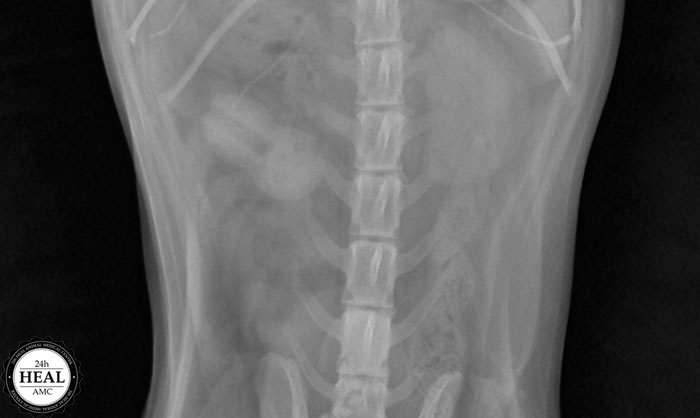

수술을 하기 전에는 반드시 상태 확인을 위한 초음파와 엑스레이 검사를 하는데

엑스레이를 찍어보니 오른쪽 상복부에 이물질이 있음을 확인한 이물질 소견이 있었습니다.

이렇게 이물질이 있는 경우 엑스레이 촬영과 초음파 검사로 진단할 수 있습니다.

이물질이 우측 신장 위와 위장 아래에 위치하고 있음을 확인할 수 있으며,

이물질의 크기는 2~3cm 정도의 크기였습니다.

이물질 감별을 위한 x선 검사와 초음파 검사를 진행하던 중 방광 측에도 결석 소견이 함께 발견되어

결론적으로 장내 이물질과 방광결석으로 진단하였습니다.